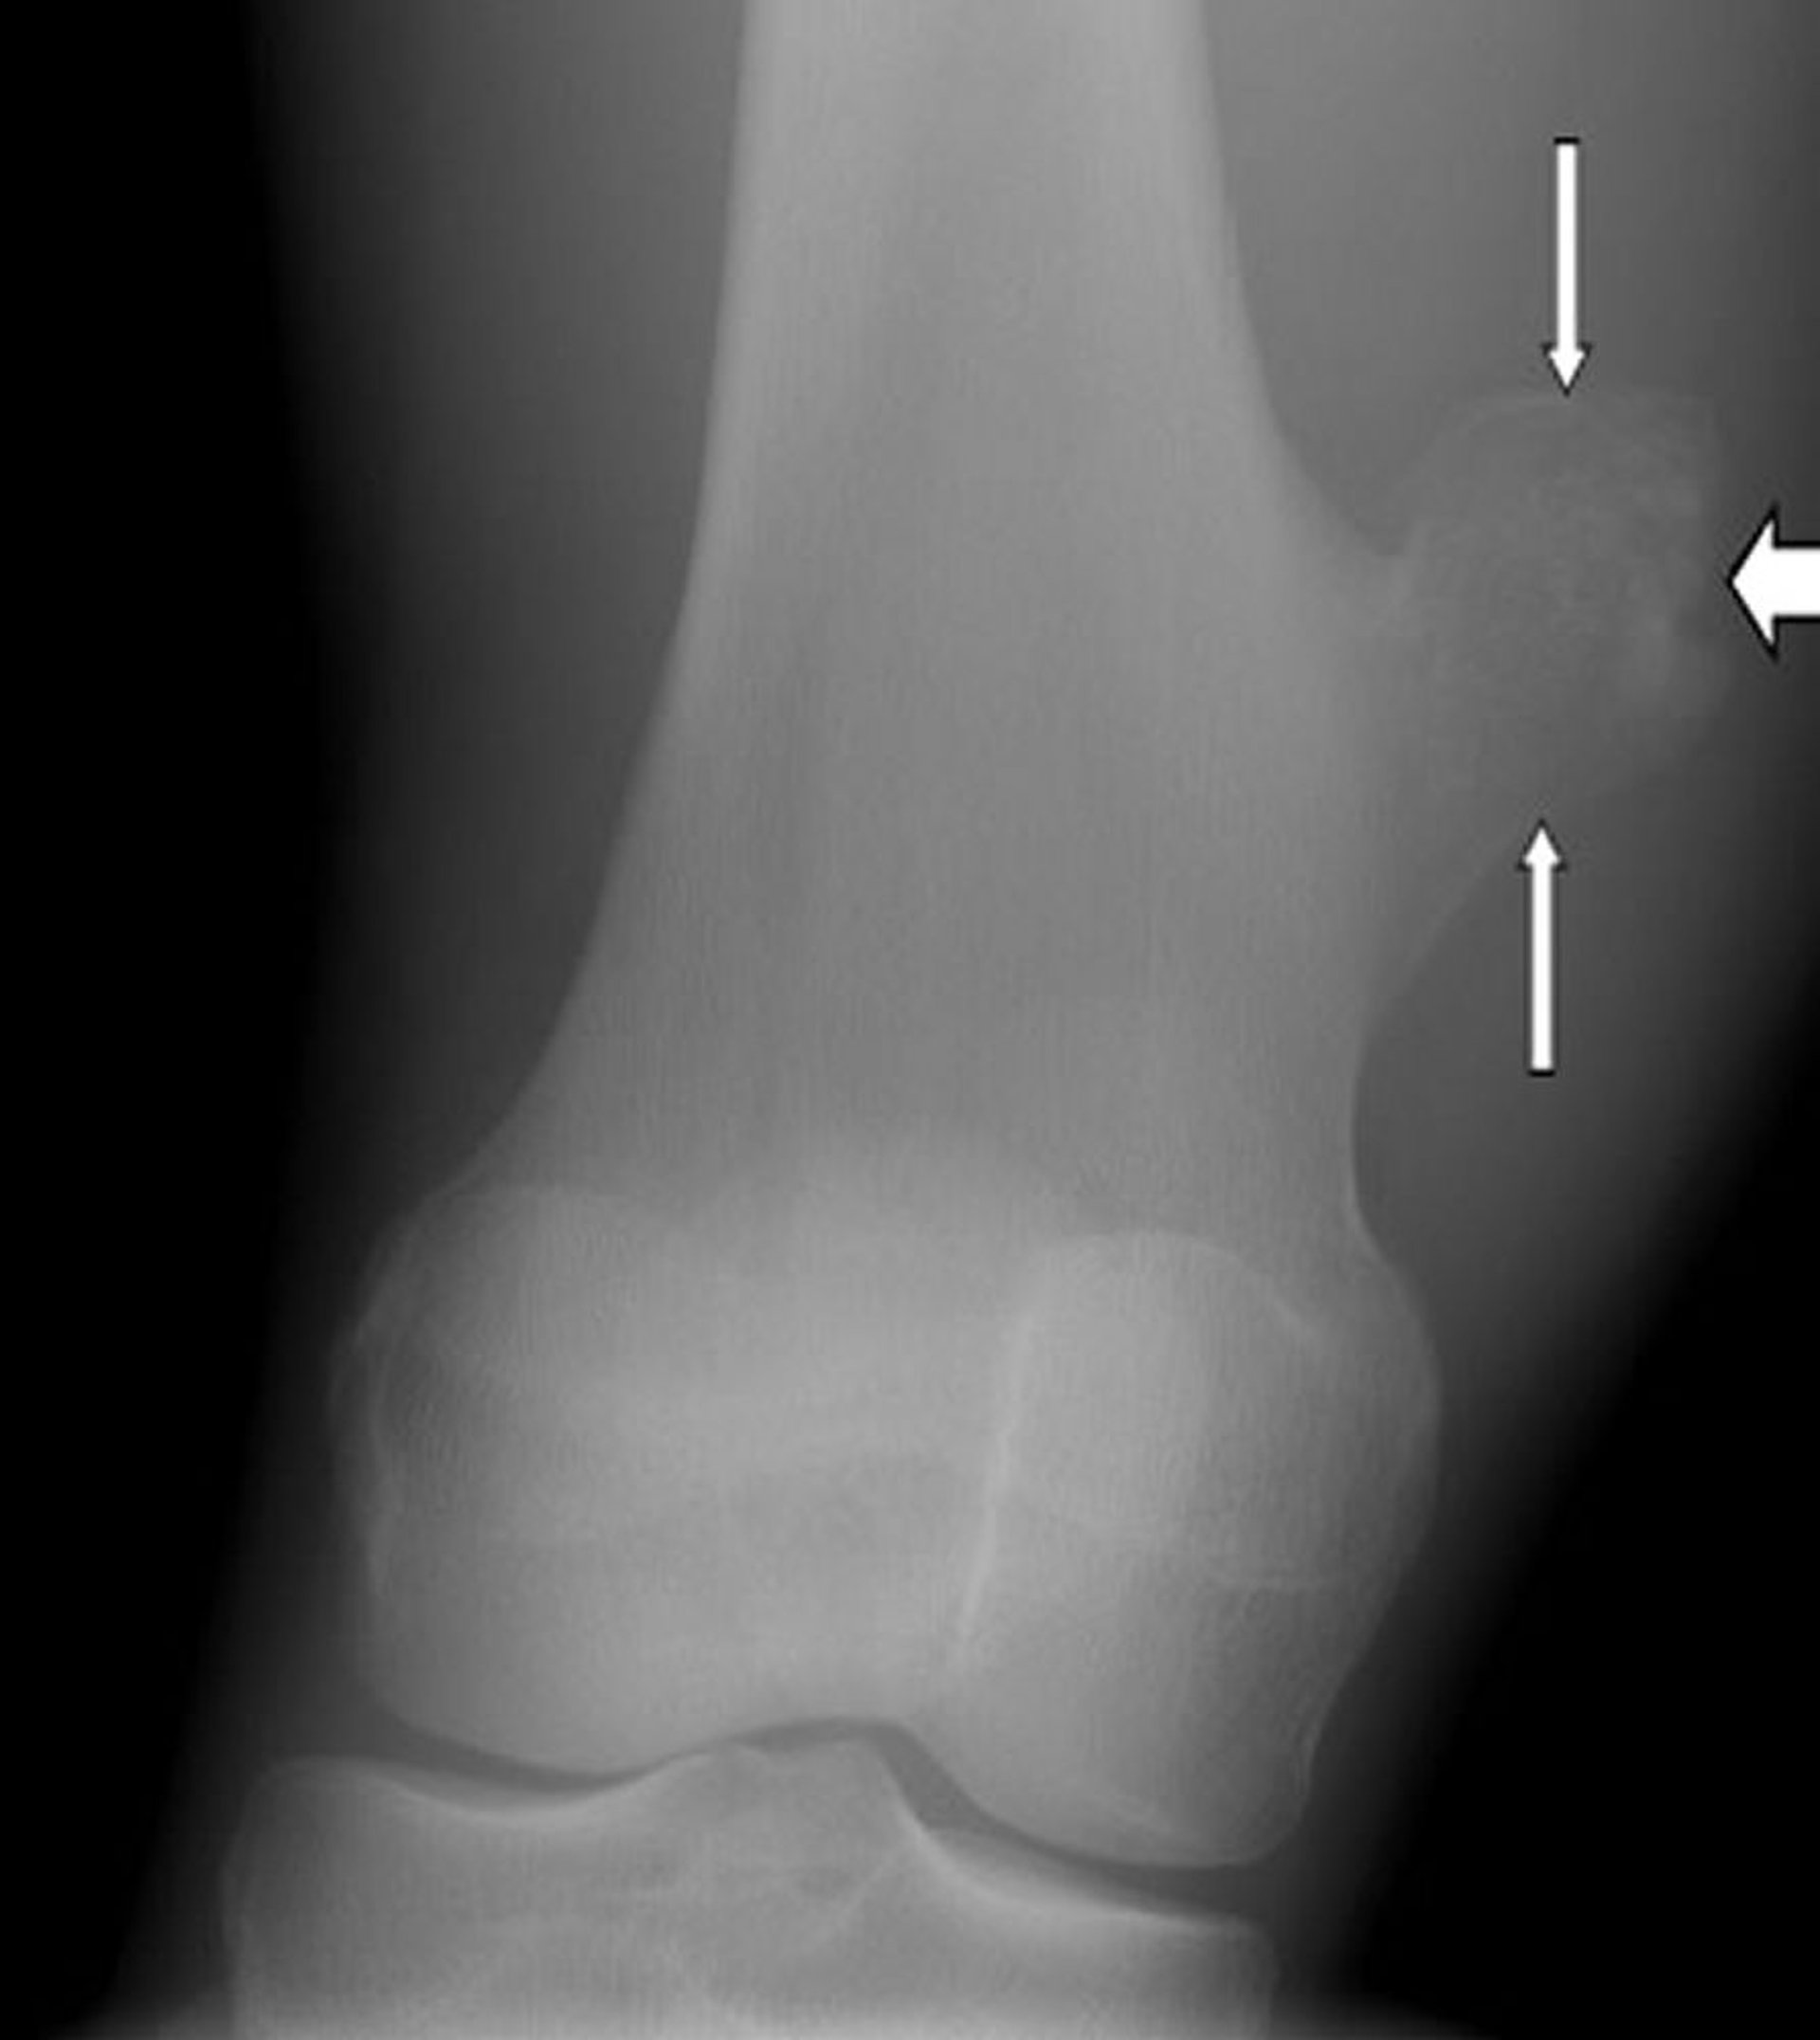

تُظهر هذه الصورة الشعاعية للركبة وجود ورم ليفي غضروفي مخاطي chondromyxofibroma (اتجاه الأسهم) في عظم الظنبوب دون مستوى الركبة.

جرى استخدام الصورة بعد موافقة أصحابها Michael J.Joyce, MD, and Hakan Ilaslan, MD.